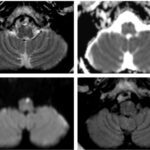

El compromiso estructural observado corresponde a una alteración del circuito dentato-rubro-olivar, cuyo daño es un mecanismo bien reconocido en la génesis de la degeneración olivar hipertrófica (DOH). En este contexto, la hiperintensidad de la oliva inferior en secuencias T2/FLAIR constituye el hallazgo imagenológico cardinal, permitiendo el diagnóstico incluso en ausencia de cambios volumétricos evidentes en fases iniciales.

La DOH representa una forma particular de degeneración transneuronal, secundaria a la interrupción de las conexiones aferentes de la oliva inferior, más frecuentemente asociada a lesiones estructurales del núcleo dentado, pedúnculo cerebeloso superior o núcleo rojo.(7) En las imágenes, este proceso se manifiesta inicialmente como un aumento de señal en T2 y FLAIR sin agrandamiento del núcleo, seguido, en fases intermedias, por incremento del volumen olivar y, finalmente, por una etapa tardía de normalización volumétrica o atrofia, con persistencia de la hiperintensidad.(8)

La identificación de estos cambios evolutivos dependientes del tiempo resulta fundamental para una correcta interpretación de las imágenes, ya que la DOH puede simular otras entidades infiltrativas o neoplásicas del tronco encefálico si no se reconoce su patrón característico.(9) En este caso, la coexistencia de una lesión estructural hemorrágica crónica en el pedúnculo cerebeloso derecho refuerza la relación causal con el compromiso contralateral de la oliva inferior.

Desde el punto de vista clínico, esta alteración anatómica se asocia clásicamente con temblor palatino sintomático, ataxia cerebelosa y alteraciones de la coordinación, aunque la expresión clínica puede ser variable y no siempre proporcional a los hallazgos en la neuroimagen.(7-9)